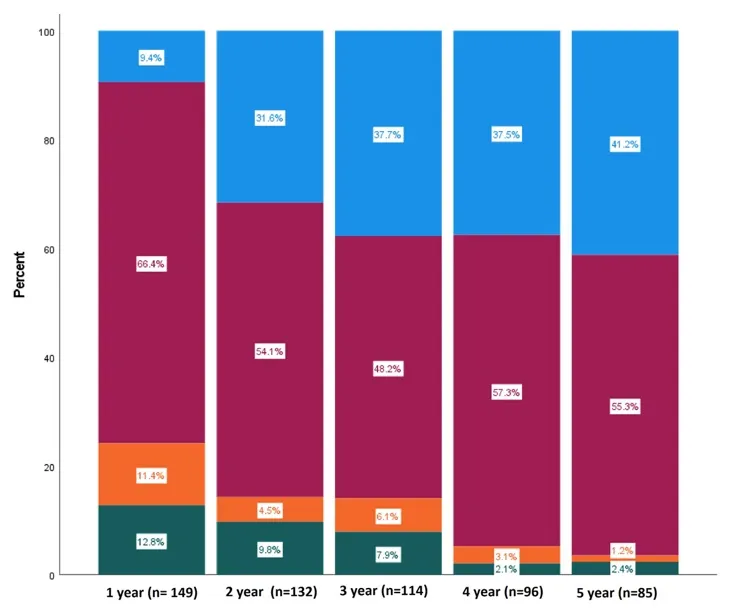

Neste vídeo, abordamos estratégias para lidar com pacientes com nefropatia membranosa que não respondem ao tratamento inicial. Ele enfatiza a importância da reavaliação constante e do ajuste do regime de tratamento com base nos resultados e no estado do paciente.

Como fazer o tratamento da Nefropatia Membranosa de forma prática!

Como fazer o tratamento da Nefropatia Membranosa de forma prática!